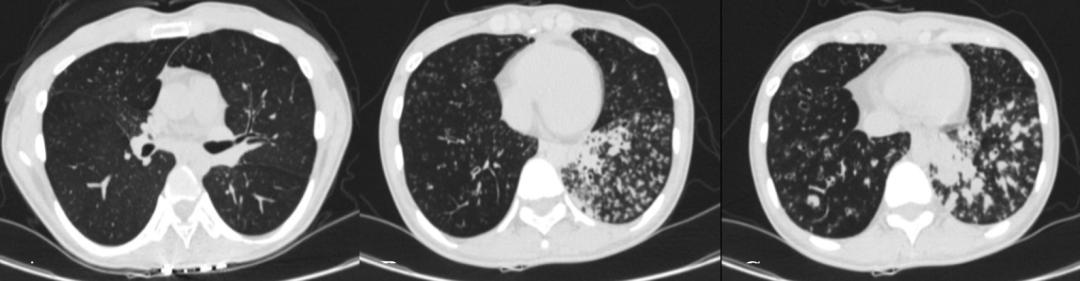

胸部CT(图1):双侧支气管扩张伴感染,结核性疾病不排外。

图1.2021年9月胸部CT

3、辅助检查:①实验室检查:WBC、N%轻度升高,CRP、真菌D-葡聚糖、内毒素试验阴性;②抗酸染色和T-SPOT阴性;③胸部CT:支气管扩张合并感染,可见「树芽征」,左下肺可见粟粒样结节;鼻窦CT:双侧筛窦、上颌窦可见黏膜增厚、水肿,未见骨质破坏,右侧筛窦较左侧病变重;④支气管镜活检组织电镜:部分上皮细胞纤毛少,有纤毛缺失、短小,未见动力臂(放大1000倍)。

3、辅助检查:①胸部CT:支气管扩张合并感染,有典型的「树芽征」,并且在左下肺可见粟粒样结节;②鼻窦CT:双侧筛窦、上颌窦可见黏膜增厚、水肿,未见骨质破坏,右侧筛窦较左侧病变重;③支气管镜活检物电镜:部分上皮细胞纤毛少,有纤毛缺失、短小,未见动力臂(放大1000倍);④全外基因检测:CCNO基因c.303C>A杂合变异以及c.248_252dup杂合变异,根据ACMG致病性证据,该变异为无功能(LOF)变异,可能导致翻译产生的蛋白截断或降解。